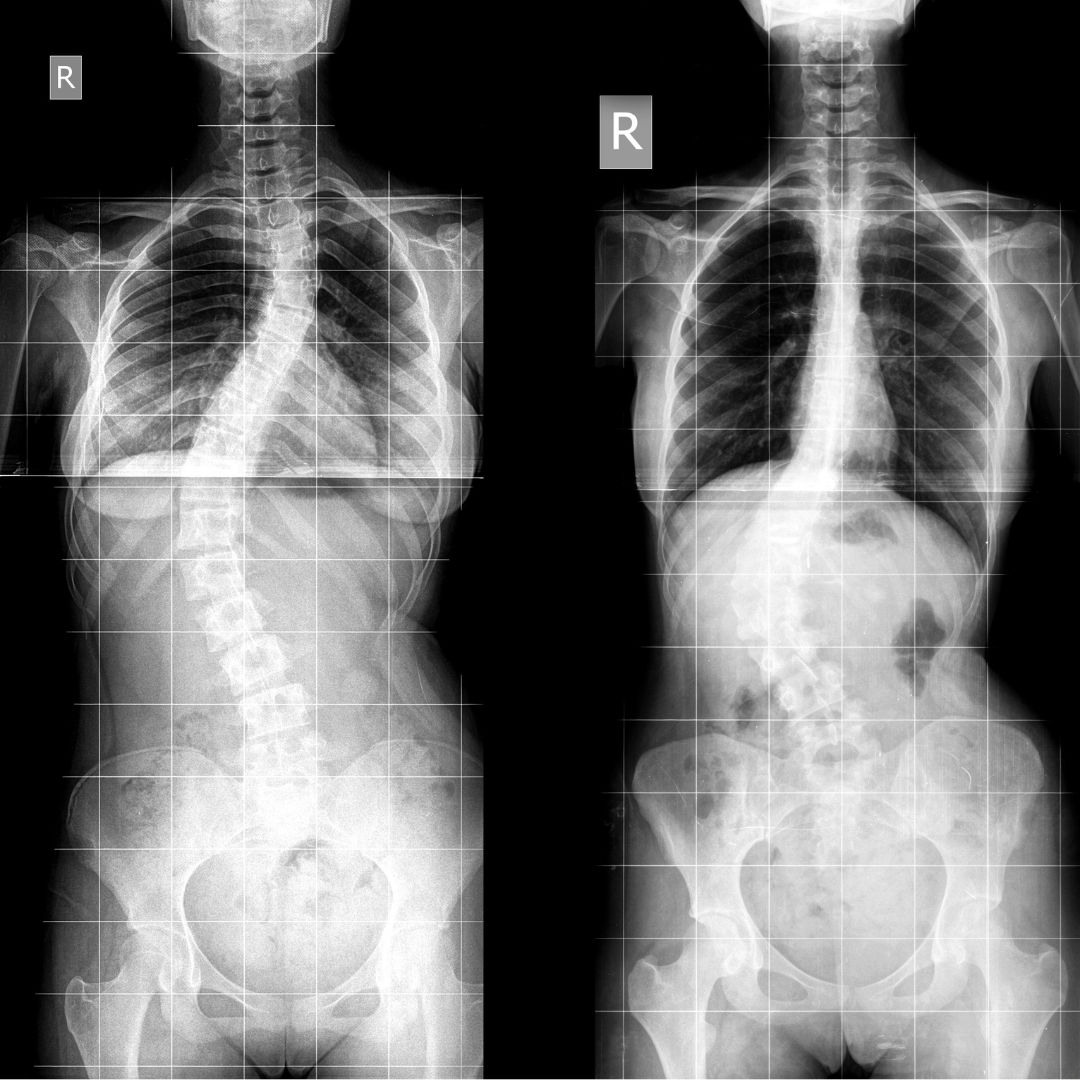

Terapia skolioz u dzieci, młodzieży i dorosłych

Skolioza to złożona, trójpłaszczyznowa wada postawy, która wymaga precyzyjnego i zindywidualizowanego podejścia na każdym etapie życia. W centrum Spinetic odchodzimy od schematycznych rozwiązań na rzecz metod o potwierdzonej skuteczności. Dzięki połączeniu wiedzy naszych fizjoterapeutów z zaawansowaną technologią, pomagamy pacjentom w każdym wieku zatrzymać progresję skrzywienia, zredukować ból i wypracować stabilną, skorygowaną postawę ciała.